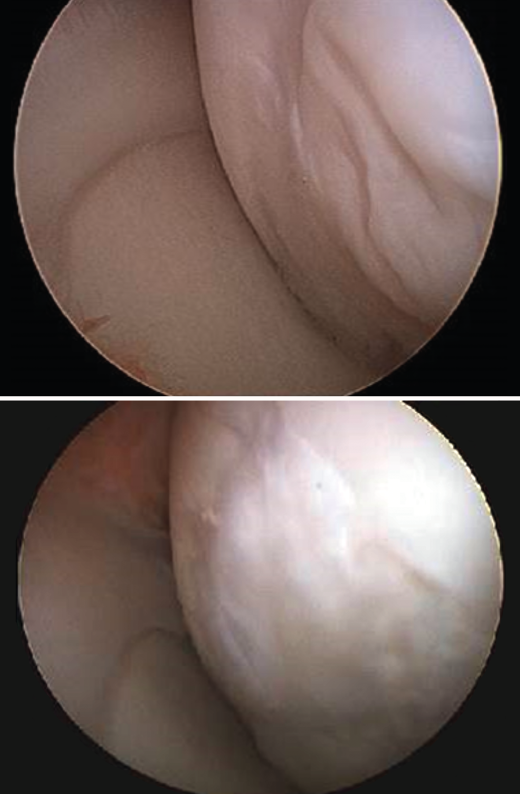

As commented above, an osteotomy is needed to access the joint, followed by reduction with osteosynthesis material during implant surgery. During withdrawal of the material, a biopsy of the newly formed tissue sometimes can be obtained. In these cases, the histological study of the biopsies of these patients confirmed the hyaline nature of the tissue, and the site of the defect was seen to be covered with newly formed tissue of characteristics similar to those of hyaline cartilage with type II collagen, in correspondence with the clinical results of the patients (Figure 20).